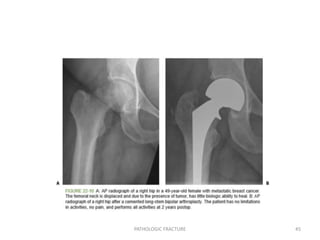

• 44.

Lower-Extremity Fractures: The femuris the most common long bone to be affected by metastasis.The proximal third is involved in 50% of cases,with the intertrochanteric region accounting for 20% of cases. Metastatic disease to the femur is the most painful of the bone metastasis, likely because of the high weight-bearing stresses through the proximal region. Painful destructive lesions in the proximal femur should be prophylactically stabilized whenever possible. Femoral Neck: Pathologic fractures of the femoral head and neck rarely heal, and the neoplastic process tends to progress. The procedure of choice:Cemented replacement prosthesis (hemiarthroplasty versus a total hip replacement depends on the presence of acetabular involvement) PATHOLOGIC FRACTURE 44

• 45.

• 46.